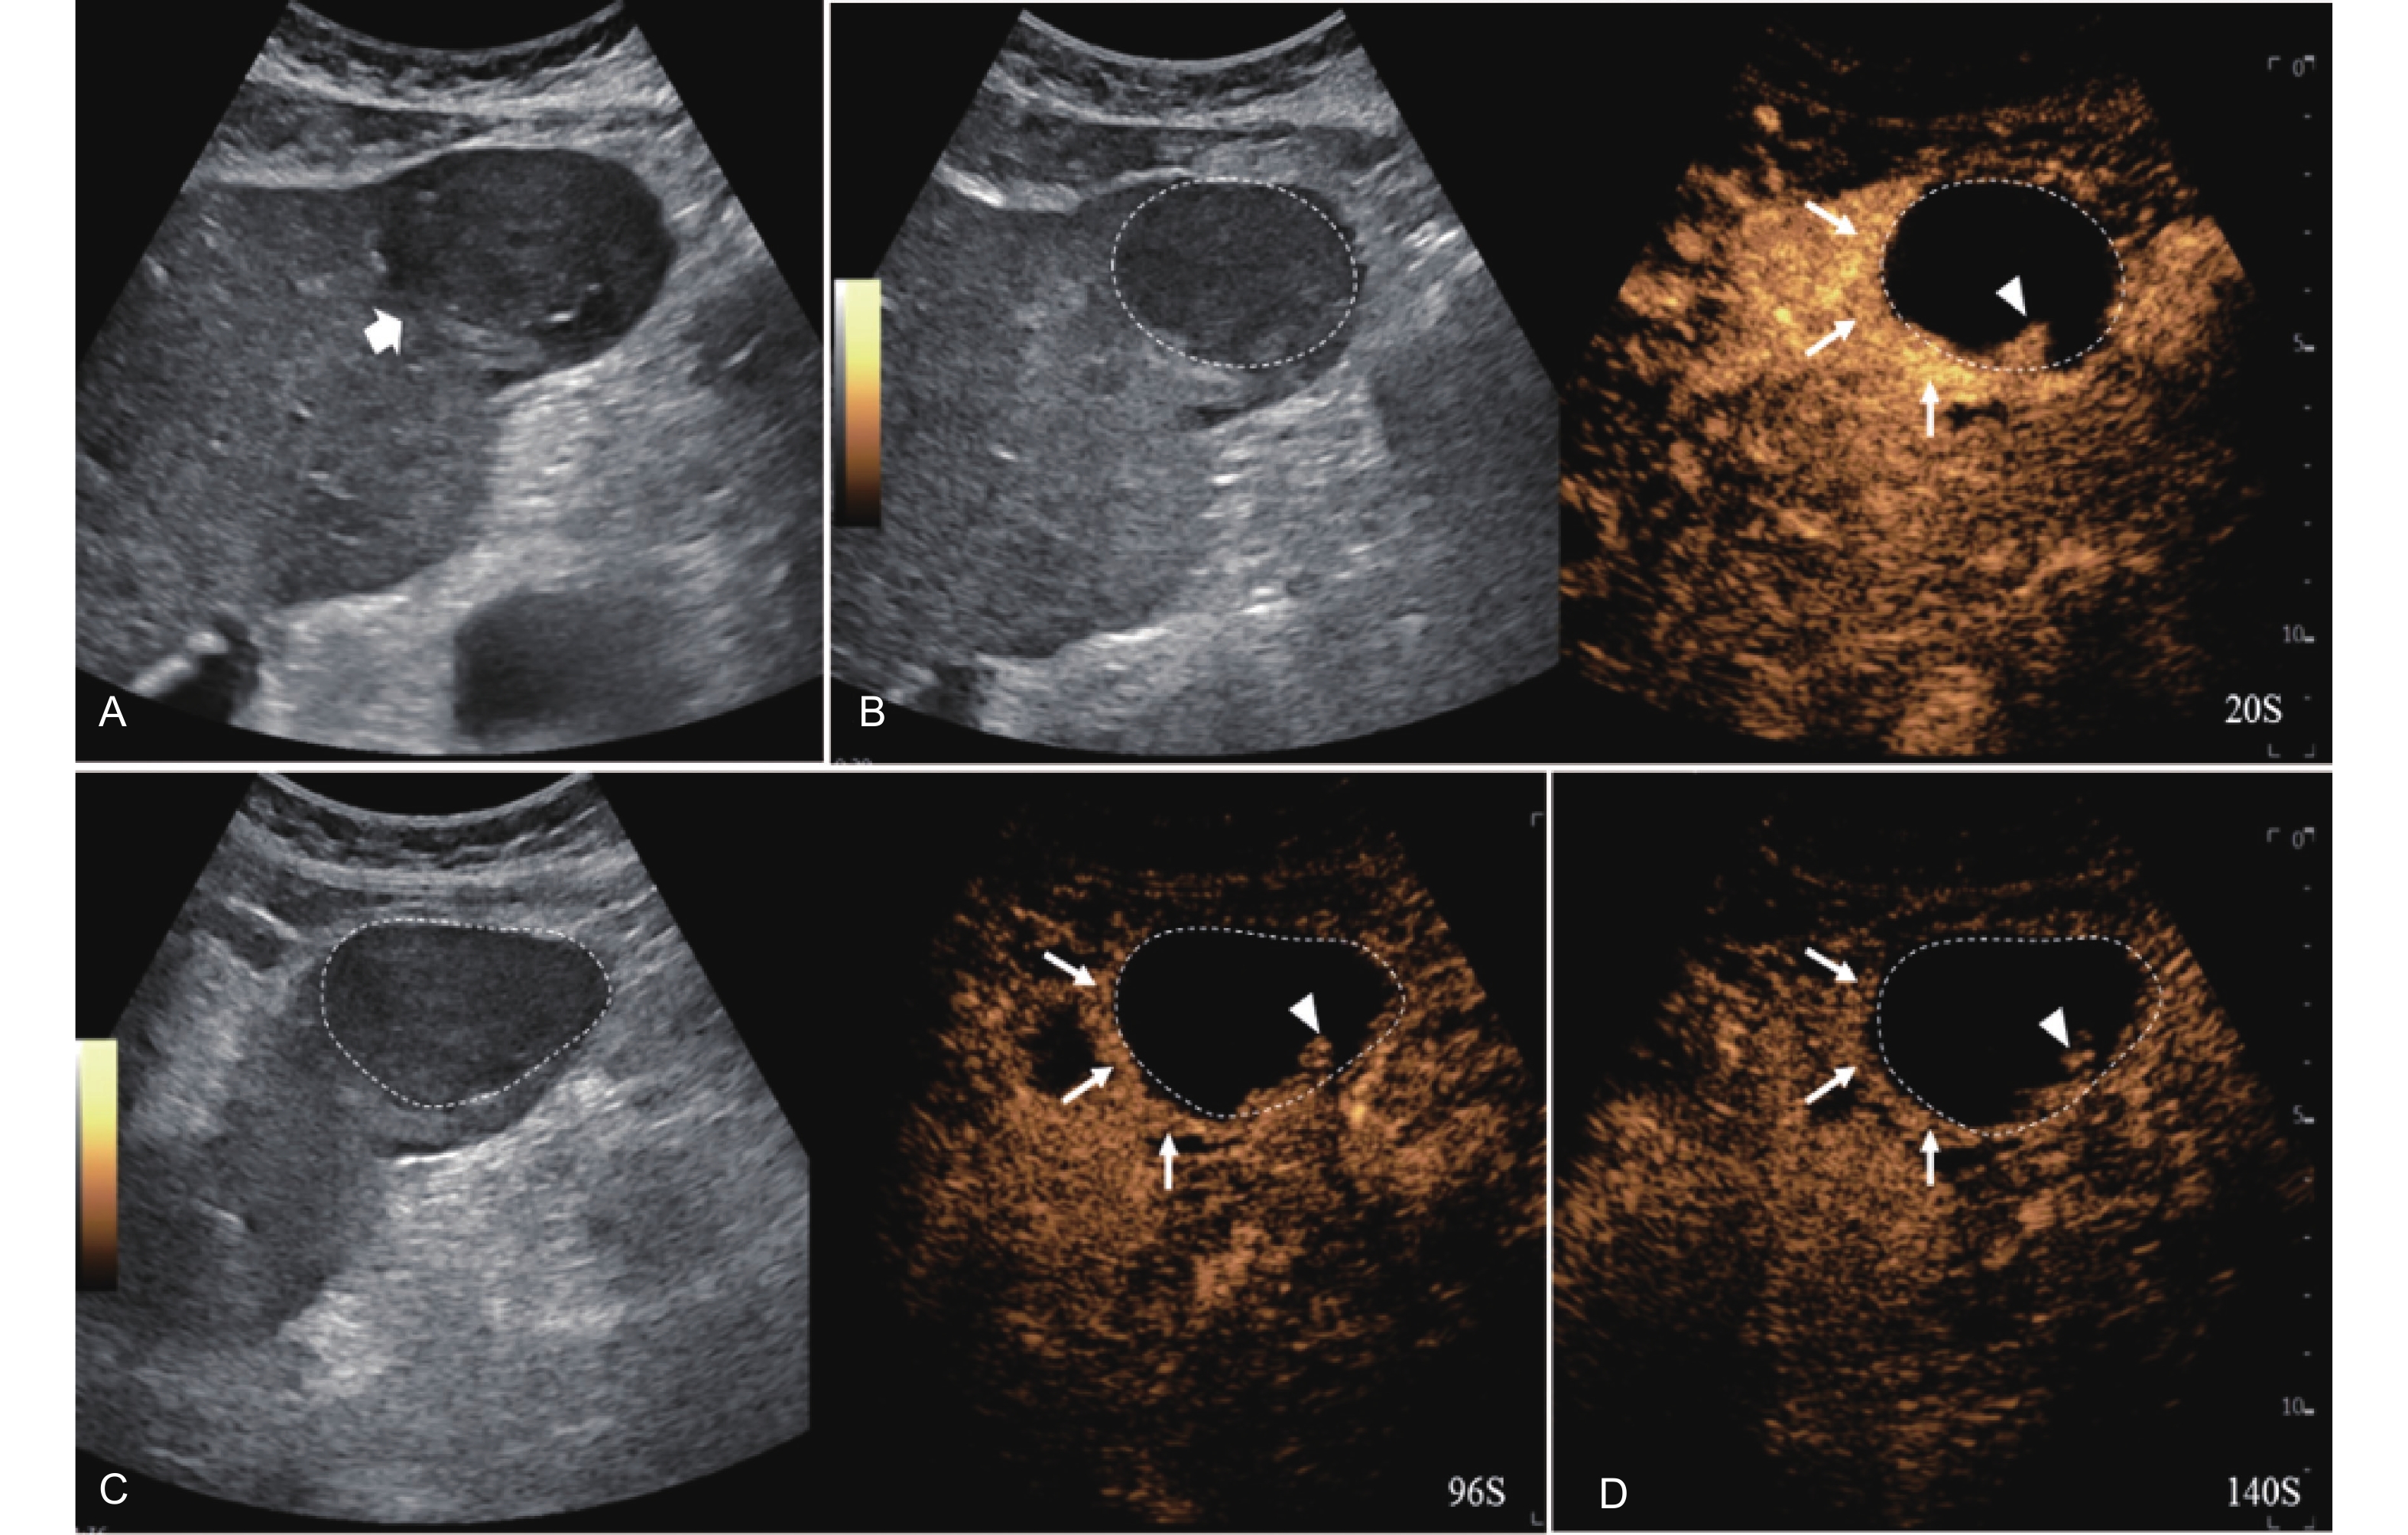

Figure 12

LR-TR Viable. Example of a treated tumor 55 days after TACE. (A) B-mode image shows a hypoechoic lesion (thick arrow) with well-defined margins, measuring 52 mm in segment III; (B) CEUS shows intralesional hyperenhancement with nodular protrusions along the margin (arrowhead) and perilesional hyperenhancement (thin arrow) during the arterial phase; (C-D) The lesion shows intralesional (arrowhead) and perilesional isoenhancement (thin arrow) without washout in the portal venous and late phases. Findings are consistent with LR-TR Viable."